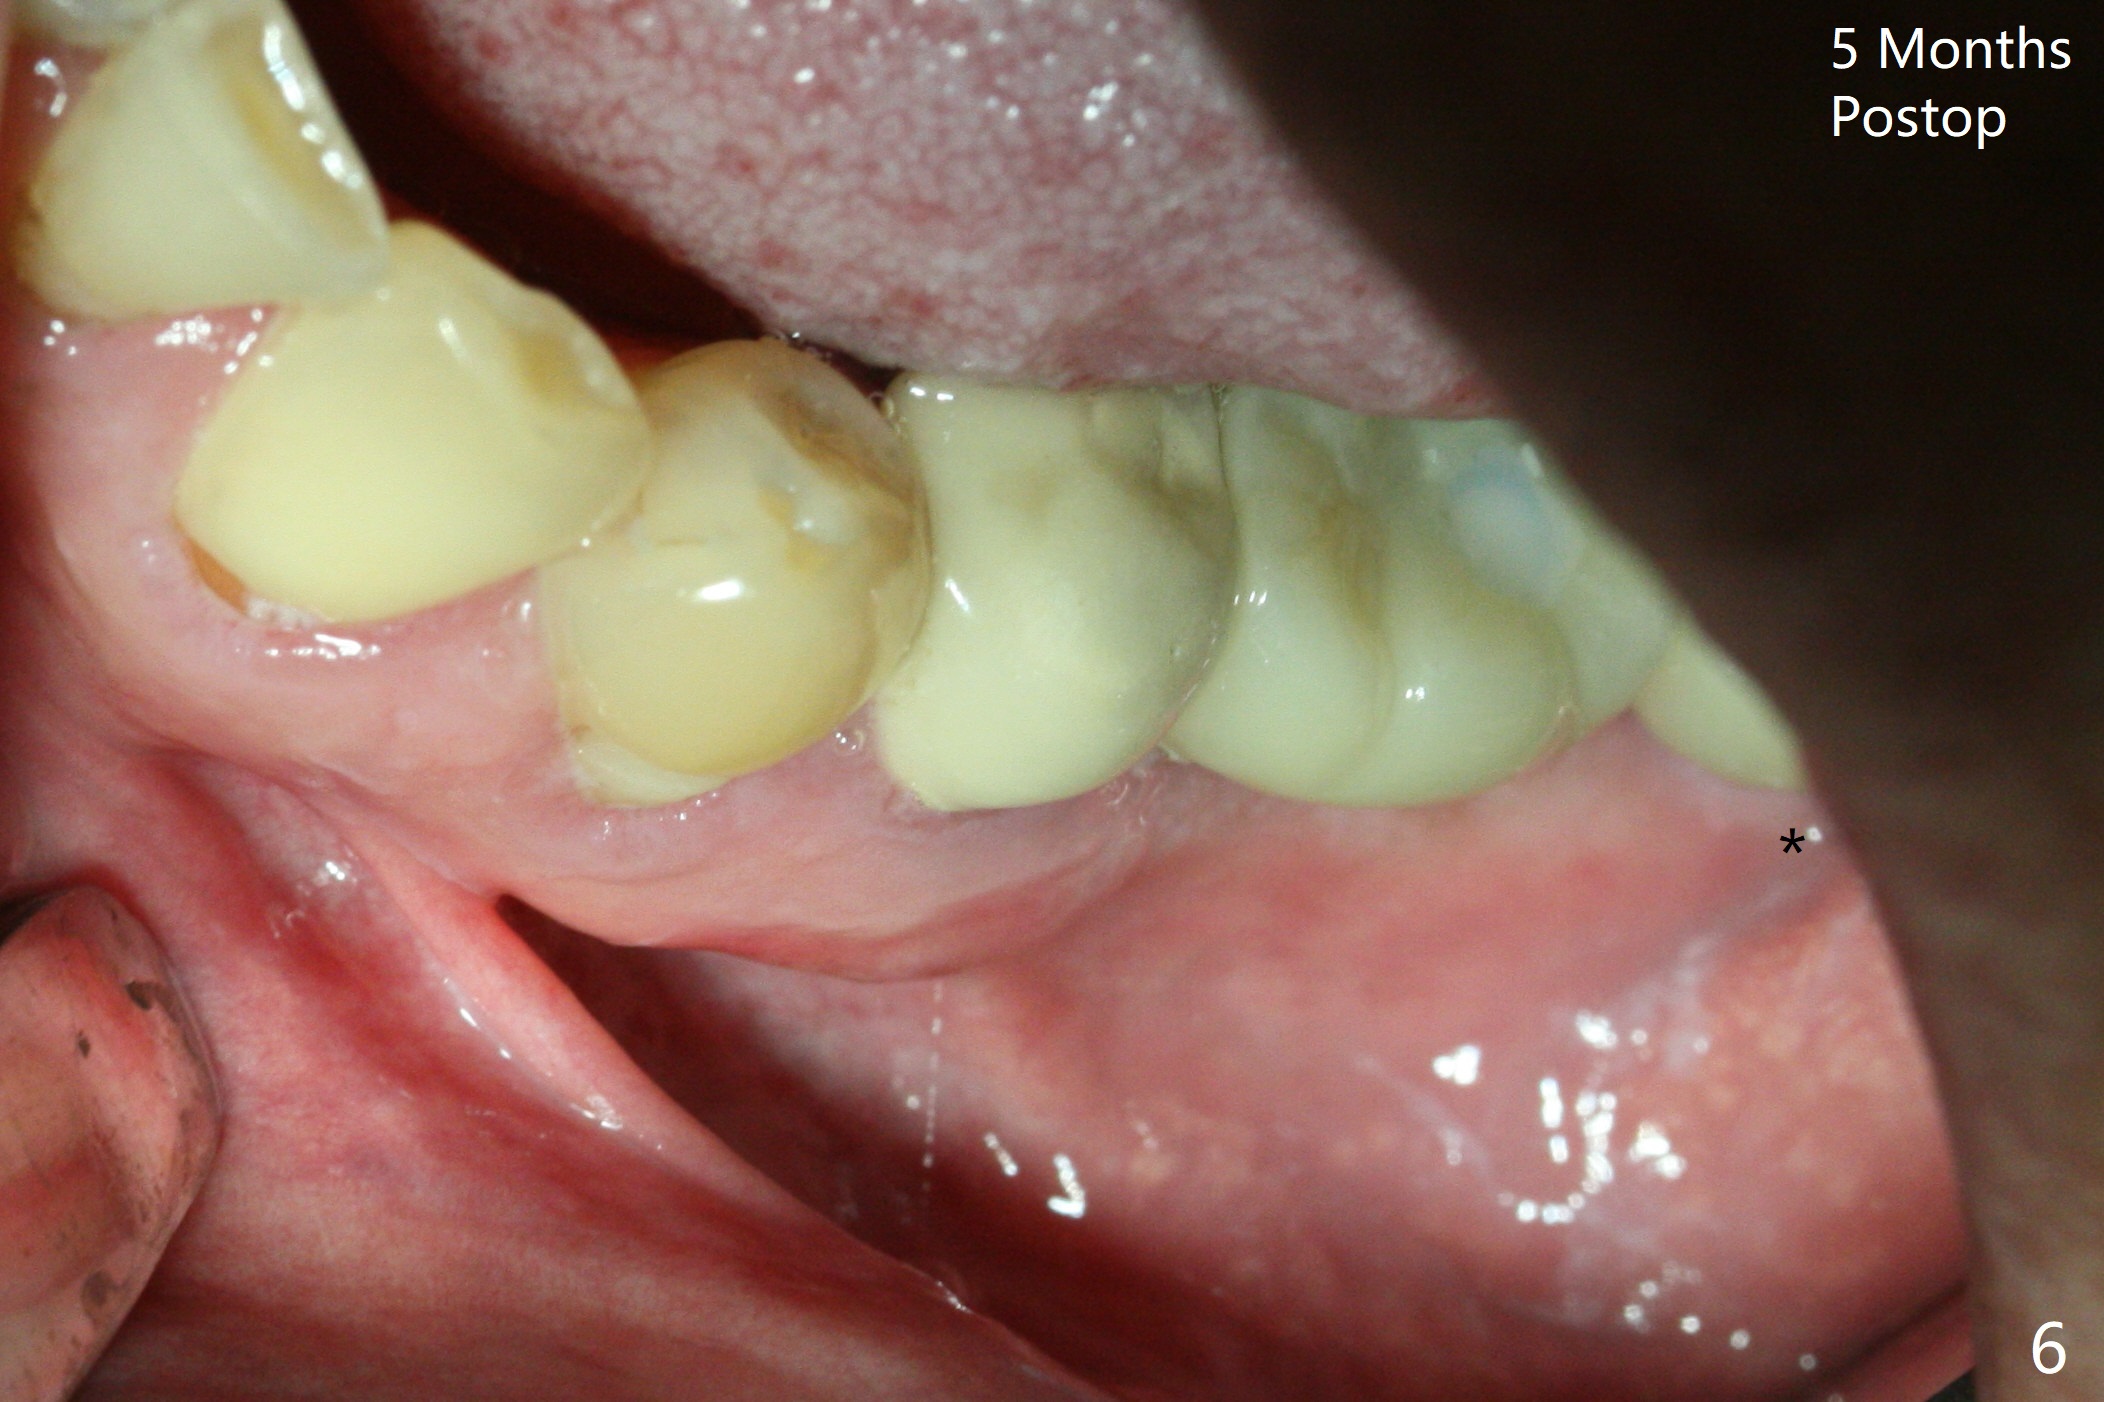

A drawback of placing an implant in the distal socket of the 2nd lower molar is closer to the Inferior Alveolar Canal.  The implants seem to have osteointegrated 4.5 months postop (Fig.5).  While the ridge at #19 appears to be wider than preop (as compared to Fig.1), that at #18 seems to be atrophic 5 months postop (Fig.6 * (1 week post cementation)).  The distal implant placement at #19 may increase possibility of abutment screw loosening during functioning (Fig.7 *).  When the patient returns for periodic exam 1.5 months post cementation, loose contact between the implant crowns is noted (Fig.8).  The bony trabeculae form between the 2 implants crestally 12 months postop, i.e., 7 months post cementation (Fig.9).  The loose contact between the 2 implants is corrected 14 months post cementation.